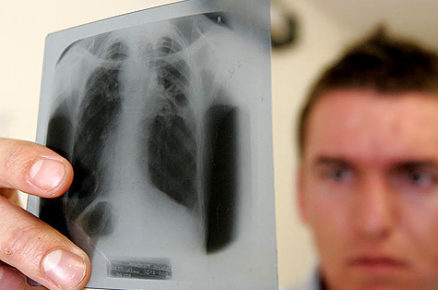

En el Día Mundial de la Tuberculosis, la Organización Mundial de la Salud (OMS) señala que la mortalidad por la enfermedad ha descendido un...